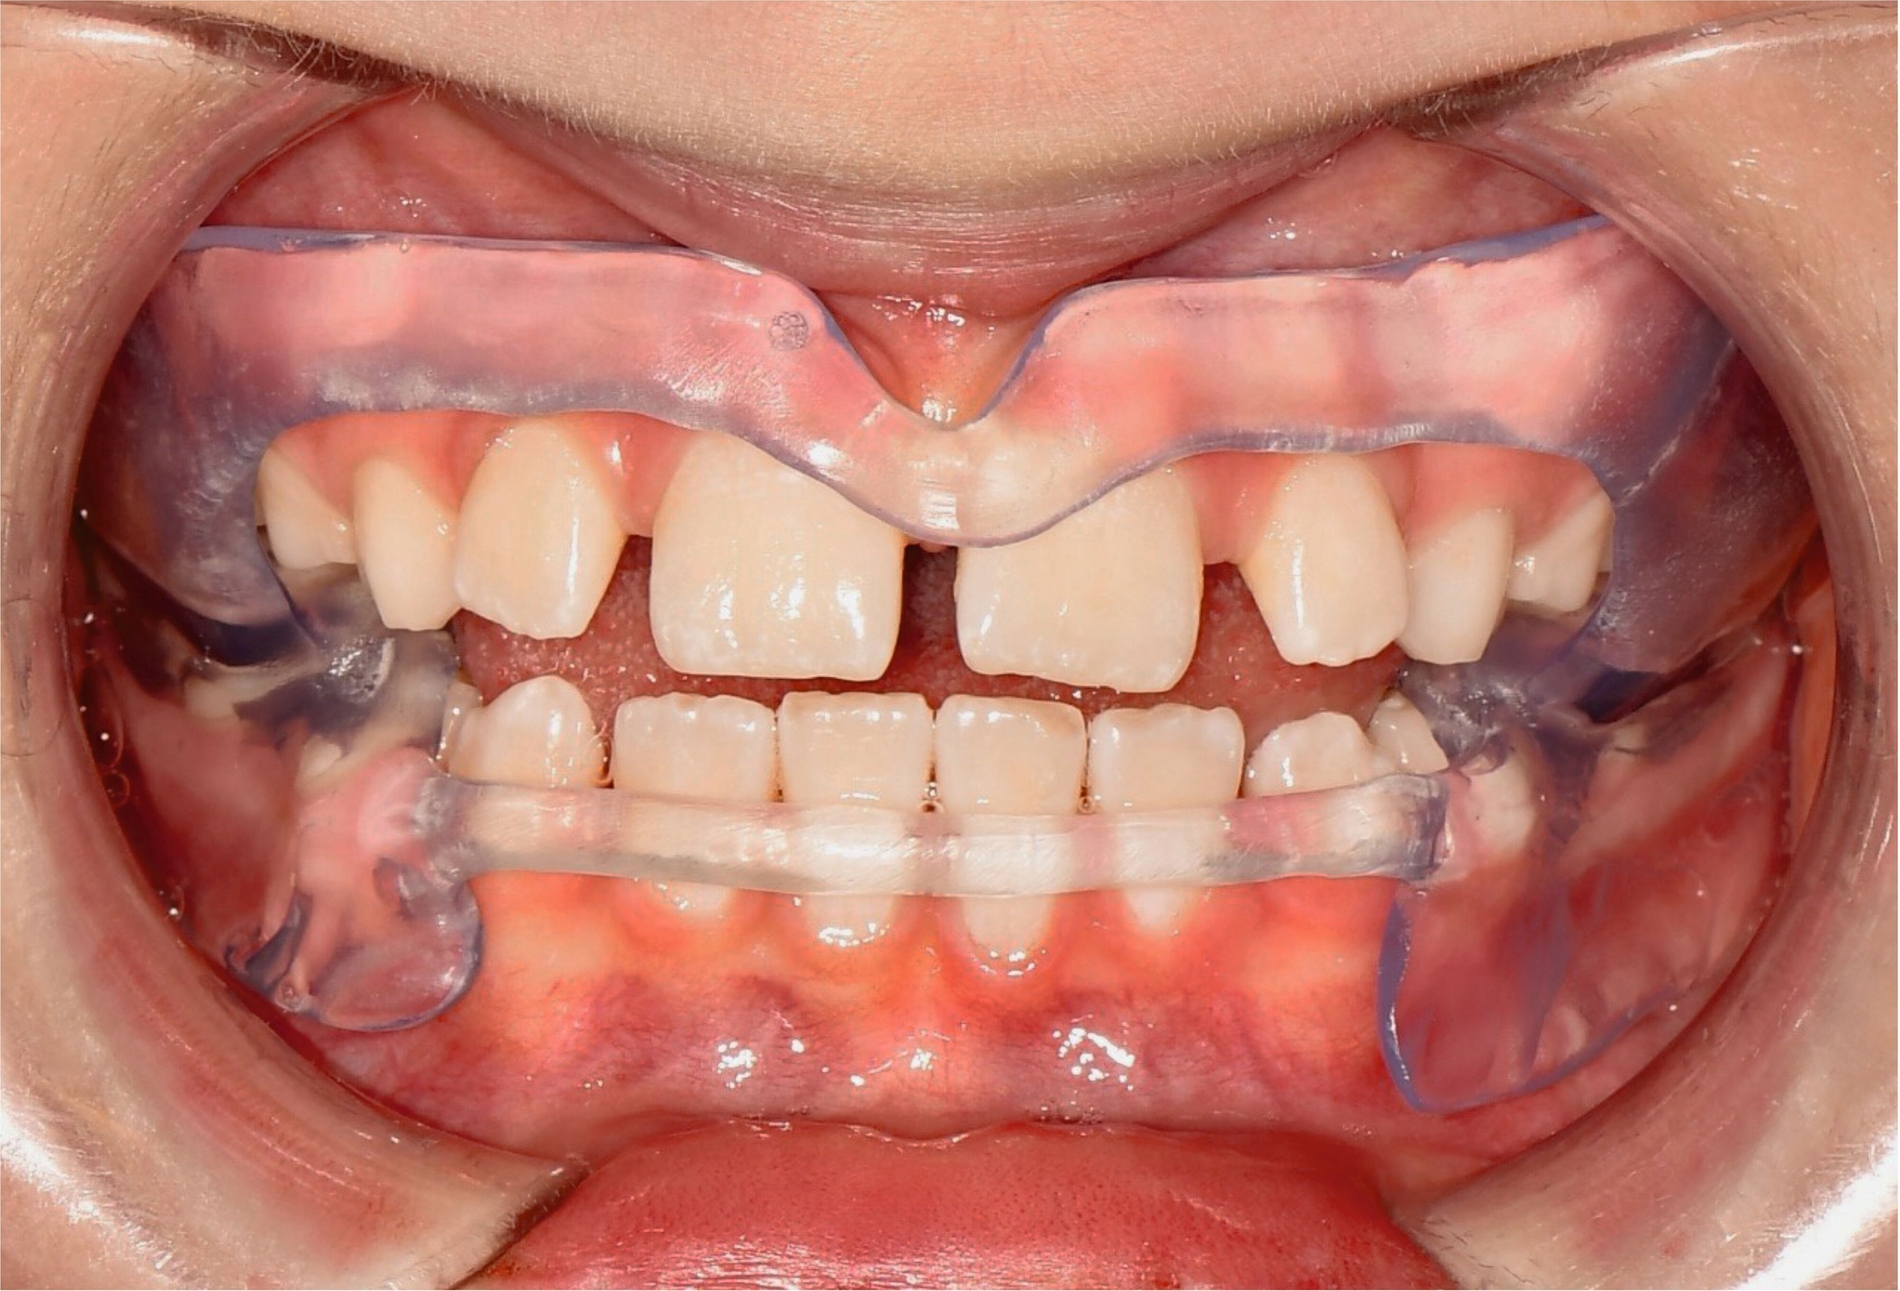

Aligner

Unter den digital gefertigten kieferorthopädischen Apparaturen sind Aligner wohl das bekannteste Beispiel [Ercoli et al., 2014, Robertson et al., 2020]. Die Herstellung von Alignern selbst basiert(e) jedoch auf einer manuellen Fertigung anhand 3-D-gedruckter Modelle und stellt(e) somit bisher eher eine partiell automatisierte Fertigung dar. Die neuesten Entwicklungen erlauben mittlerweile eine Fertigung im direkten 3-D-Druckverfahren [Tartaglia et al., 2021], so dass mühsame, zeitaufwendige Zwischenschritte der manuellen Fertigung entfallen (Abbildung 1a). Weiter profitieren die Patienten von individuelleren Fertigungsmöglichkeiten, da durch die Umsetzung im 3-D-Druck zusätzliche Elemente einfacher und stabiler in den Aligner inkorporiert werden können (Abbildung 1b).